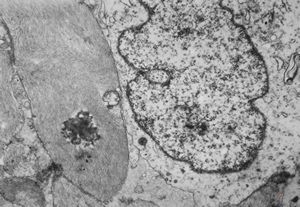

F,49y. | purulent meningitis- meningococcal v.s.